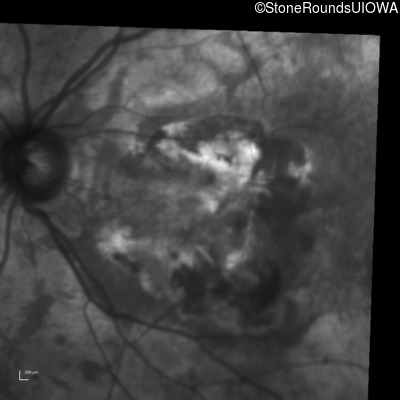

Infrared Fundus Photograph - Right - 20/200 +2

Exemplar